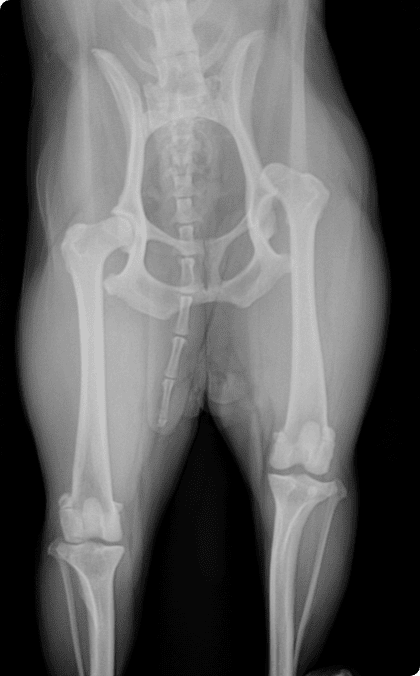

골절은 반려동물에서 흔히 발생하는 정형외과 질환으로

단순 골절부터 복합 골절까지 형태와 정도가 다양하며

주변 근육·혈관·신경 손상이 동반될 수 있어

신속하고 정밀한 치료가 필요함.